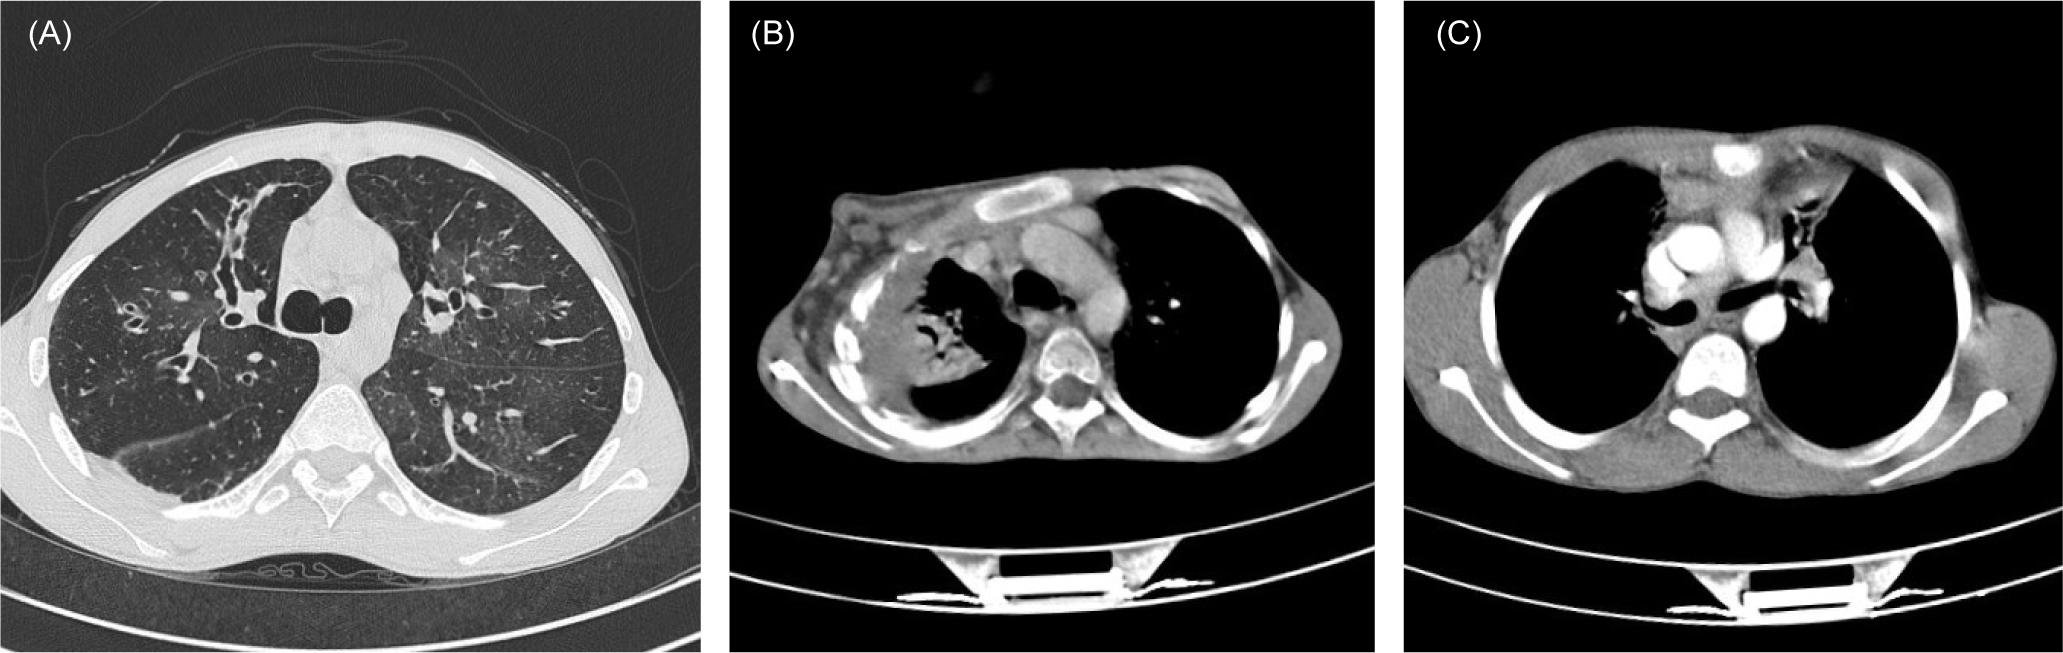

Bronchiectasis (n = 28, 58.3%) was the most common HRCT scan finding (Figure 1A), followed by bronchial wall thickening (n = 11, 22.9%) and consolidation (n = 9, 18.8%). Bronchiectasis complicated 25 (58.1%) CVID, one HIGM, both XLA patients, and was bilateral in 64.3% (18 of 28) of them. The most frequent site of bronchiectasis in all patients with PAD was the right middle lobe. Overall, PFTs exhibited an obstructive pattern in 10 (31.3%), restrictive pattern in 8 (25%), and mixed pattern in 2 (6.2%) patients. Ten out of 29 CVID patients (34.5%) with available PFT displayed a purely obstructive pattern , while five (17.2%) and two (7.4%) CVID patients had restrictive and mixed pattern, respectively. All patients with HIGM and XLA had a restrictive pattern.

Figure 1 Axial chest HRCT images depicting the most common findings in patients with inborn errors of immunity. (A) Tubular and varicoid bronchiectasis and patchy ground-glass opacities in bilateral middle and lower lung lobes of a patient with X-linked agammaglobulinemia (XLA). (B) Focal collapse consolidation with invasion to the chest wall and associated osteolytic bone lesions in a patient with CGD. (C) Bilateral mediastinal lymphadenopathy in a patient with MSMD.

Consolidation (n = 17, 44.7%), bronchiectasis (n = 11, 28.9%), and nodular infiltration (n = 11, 28.9%) were the most reported finding in CGD patients, especially in the right upper lobe of the lung (Figure 1B). A mixed restrictive–obstructive pattern in PFT was the most common (n = 8, 21%). The patient with congenital cyclic neutropenia suffered from productive cough, dyspnea, sinusitis, and perianal abscess, and presented with nodular infiltration in the HRCT and obstructive pattern in the PFT.

Eight (50%) male and eight (50%) female patients with MSMD were found. Among the diagnostic groups, MSMD patients had the earliest age of onset (0.5 year) and diagnosis (4.5 years), with a mean diagnostic delay of 4.7 years. Thirteen (81.2%) patients were born to consanguineous families. Patients with MSMD presented with cough (n = 4, 25%), dyspnea (n = 2, 12.5%), and sputum (n = 1, 6.2%), and pulmonary manifestation was limited to recurrent pneumonia (n = 3,18.8%) with no signs of sinusitis or otitis. Lymph node involvement was observed in all patients in axillary (75%), mediastinal (12.5%), upper abdominal (31.2%), and cervical (12.5%) regions. Consolidation (n = 3, 18.8%) and mediastinal lesions (n = 8, 18.8%) were the most reported HRCT scan findings (Figure 1C).